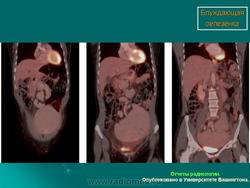

Полиспления

ID: 12761 Polysplenia syndrome , situs ambiguous, rectal mass Dr Amro Nazih Omar - 7 Jan 2011 Axial CECT demonstrates polysplenia, situs ambiguous, absent IVC an...